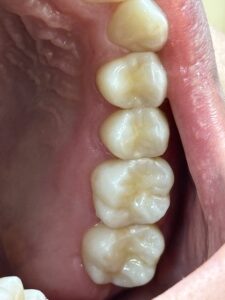

歯の神経を取る根の治療 根管治療をすれば治ります。治した後は 保険適応でハイブリッドセラミックやCAD/CAM冠インレー クラウンなどで白い歯で治すといいですね。もちろんセラミックやジルコニアの治療もあります。